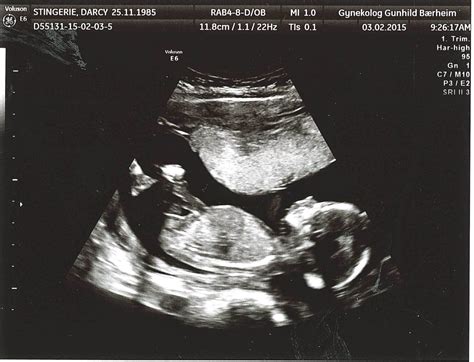

Pregnancy is an exciting journey filled with milestones, and one of the most anticipated moments is the 16 week sonogram. This ultrasound scan provides a wealth of information about the baby's development and the mother's health. Understanding what to expect during a 16 week sonogram can help alleviate anxiety and prepare parents for this important check-up.

A 16 week sonogram is an ultrasound examination performed around the 16th week of pregnancy. It is typically part of the routine prenatal care and is often referred to as the anatomy scan. This scan is crucial for assessing the baby’s growth, checking for any potential abnormalities, and providing a clearer picture of the baby’s development.

During the 16 week sonogram, the mother will lie on an examination table, and a gel will be applied to her abdomen. A transducer, a device that emits sound waves, will be moved over the abdomen to capture images of the baby. The procedure is painless and typically takes about 20-30 minutes.

• Size and Weight: The baby is about the size of an avocado, measuring approximately 4.5 to 5.4 inches (11.4 to 13.7 centimeters) in length and weighing around 3.5 ounces (100 grams).